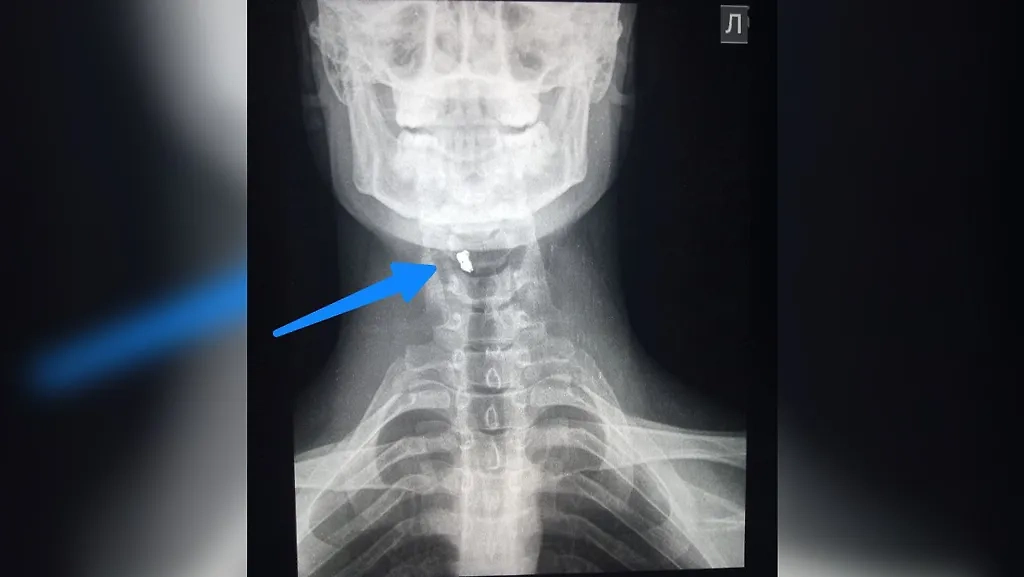

Хирург группы медицинского отряда спецназначения Сергей Кучиц поделился медицинской историей с передовой, которую можно отнести к огромной удаче. Воин-доброволец получил осколочное ранение шеи в результате взрыва боеприпаса, сброшенного с вражеского дрона. Осколок размером 10х5 мм пробил защиту и угодил чётко в проекцию позвоночника и спинного мозга, погрязнув в мягких тканях шеи.

Осколок размером 10х5 мм пробил защиту и застрял в мягких тканях шеи. Фото © Telegram / KUCHITS MED

Считаные миллиметры отделяли бойца от гарантированной смерти или тяжелейшей инвалидности. Фото © Telegram / KUCHITS MED

"Если бы боец не носил защиту шеи с бронежилетом или осколок сохранил больше энергии, то был бы перелом позвоночника с разрушением спинного мозга и, возможно, с повреждением пищевода и трахеи. Это гарантированная смерть или тяжелейшая инвалидность", — поведал военный хирург у себя в телеграм-канале.

Солдату-везунчику обработали рану, удалили осколок, провели обезболивание, антибактериальную и противовоспалительную терапию. Пациента эвакуировали для лечения в медроту, но уже через неделю – полторы он сможет вернуться в строй.